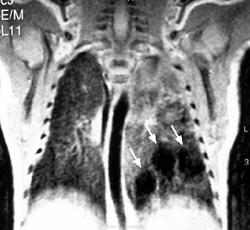

Секвестрация легкого

На компьютерных томограммах в заднемедиальном отделе нижней доли левого легкого виден участок повышенной воздушности, легочный рисунок в нем деформирован, не прослеживаются просветы сегментарных бронхов, нет дренирующего бронха.

"Секвестрированный" участок в заднемедиальном отделе нижней доли левого легкого кровоснабжается аномальной артерией, отходящей от аорты.